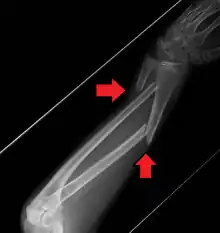

Midshaft fracture of the radius and ulna

A fracture of the forearm can be classified as to whether it involves only the ulna (ulnar fracture), only the radius (radius fracture), or both radioulnar fracture.

For treatment of children with torus fractures of the forearm splinting appears to work better than casting.[7] Genetically determined disorders like hereditary multiple exostoses can lead to hand and forearm deformities. Hereditary multiple exostoses is due growth disturbance of the epiphyses of the radius and ulna, the two bones of the forearm.[8]